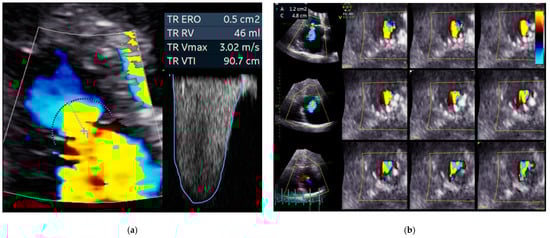

3.1. Echocardiography